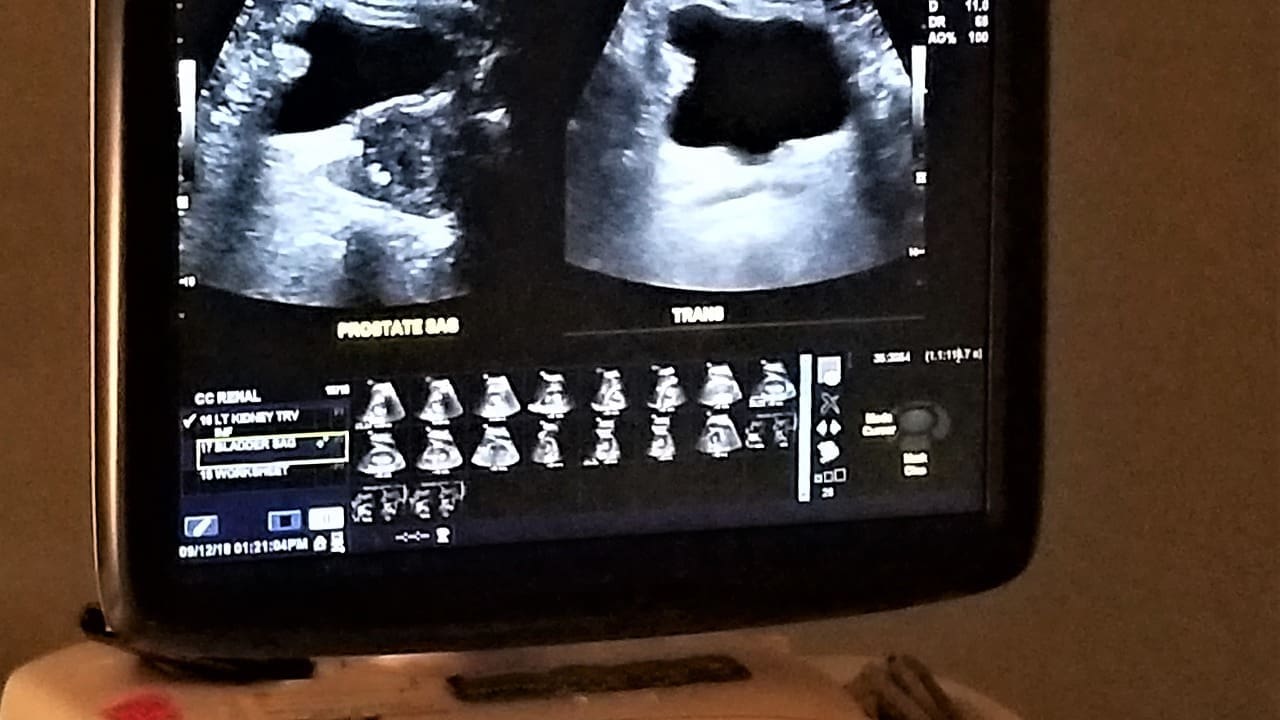

Ultrasound screening is the first choice for finding abdominal aortic aneurysms. This method is safe and works well for spotting AAAs early on. It’s a big help in catching this serious condition before it gets worse.

Ultrasound uses sound waves to see inside the body. Doctors use it to check the aorta’s size and look for any bulges. It’s easy, doesn’t hurt, and doesn’t use harmful radiation.

Ultrasound beats other methods like CT scans or MRI in many ways. It’s easy to use, doesn’t cost much, and doesn’t need special dyes or radiation. This makes it great for checking lots of people and for keeping track of changes over time.

Ultrasound is very good at finding AAAs. It has high sensitivity and specificity rates. The Canadian Society for Vascular Surgery says it’s almost 100% accurate. This is key for catching and treating AAAs early.

In short, ultrasound screening is key for finding and managing abdominal aortic aneurysms. Its safety and high accuracy make it the top choice for first checks.